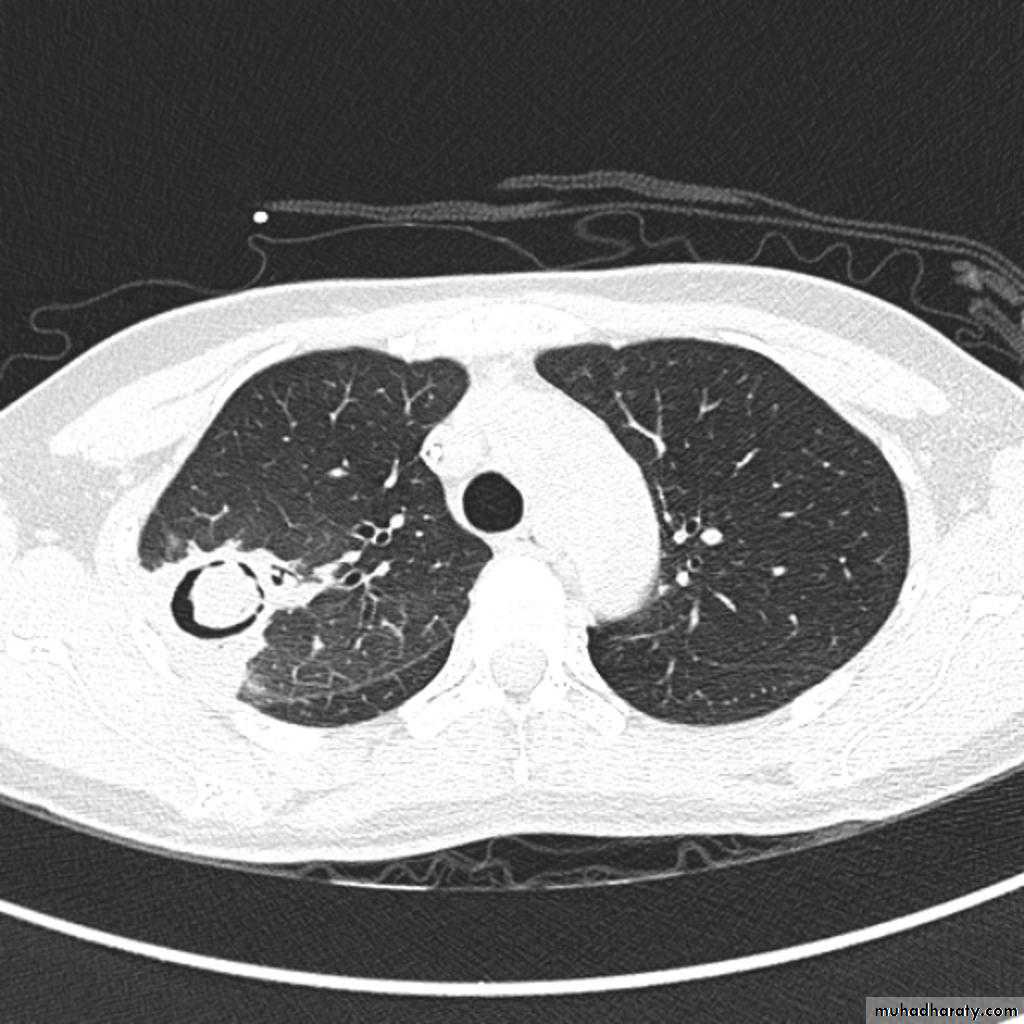

BronchiectasisMany curvilinear opacities in right lung with multiple air fluid levelsHoney comb shadow, Increase in bronchoalveolar markingsPulmonary vasculature appears ill defined